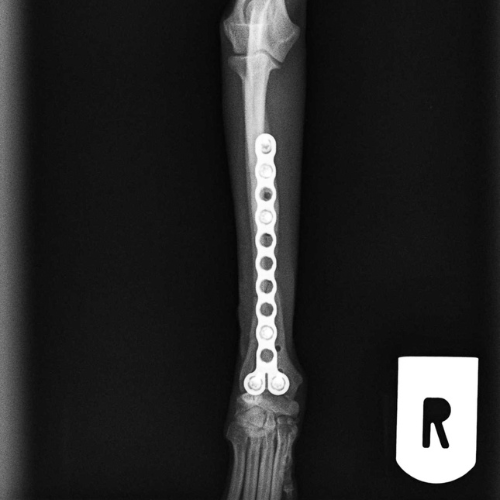

El servicio de traumatología está dirigido por Enrique Senís, especialista en traumatología y ortopedia por la Universidad Complutense de Madrid . Estamos orientados al diagnóstico y tratamiento de patologías del sistema musculoesquelético, incluyendo fracturas, luxaciones, rotura de ligamento cruzado y demás alteraciones articulares y deformidades óseas.

Disponemos de medios diagnósticos avanzados y aplicamos técnicas quirúrgicas de última generación en osteosíntesis, estabilización articular y corrección de deformidades, con el objetivo de restaurar la funcionalidad y minimizar el dolor en nuestros pacientes.